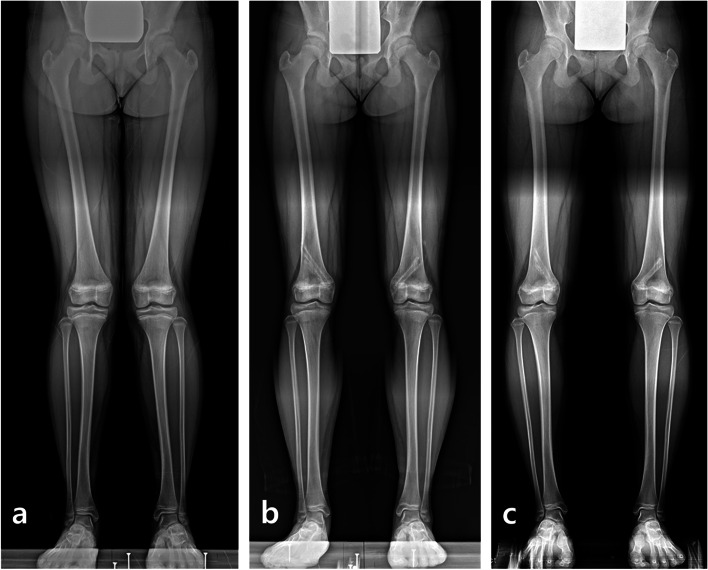

Fig. 3.

Changes in the mLDFA of distal femurs treated with PETS and TBP.

Fig. 4.

An 11-year-old girl had bilateral genu valgum with a mechanical lateral distal femoral angle (mLDFA) of 82.6° on the right and 80.4° on the left (a). Satisfactory alignments were achieved at 6.5 months after percutaneous hemiepiphysiodesis using transphyseal screws, and the alignment was well maintained 2 weeks after implant removal with a mLDFA of 87.5° on the right and 88° on the left (b). One year after implant removal, overcorrection of the distal femur was occurred with a mLDFA of 91° on the right and 89.5° on the left, and the mechanical axis deviation increased 22.8 mm and 15.2 mm, respectively (c)

In the tibias, the mMPTA of thirteen treated with PETS improved from 92.4 ± 2.9° (range, 89.7 to 97.4°) preoperatively to 87.1 ± 2.3° (range, 83.6 to 90.7°) at implant removal, and from 93.6 ± 2.8° (range, 88.3 to 98.4°) to 87.2 ± 2.3° (range, 83.2 to 91.1°) in ten tibias treated with TBP (Fig. 5). The mean mMPTA was maintained at 87.1 ± 2.5° (range, 83.9 to 92.9°) in the PETS group and increased to 89.1 ± 3.3° (range, 84.2 to 95.5°) in the TBP group at the final follow-up, but there was no significant difference in both groups (p = 0.988 and 0.070, respectively).

Fig. 5.

Changes in the mMPTA of proximal tibias treated with PETS and TBP.